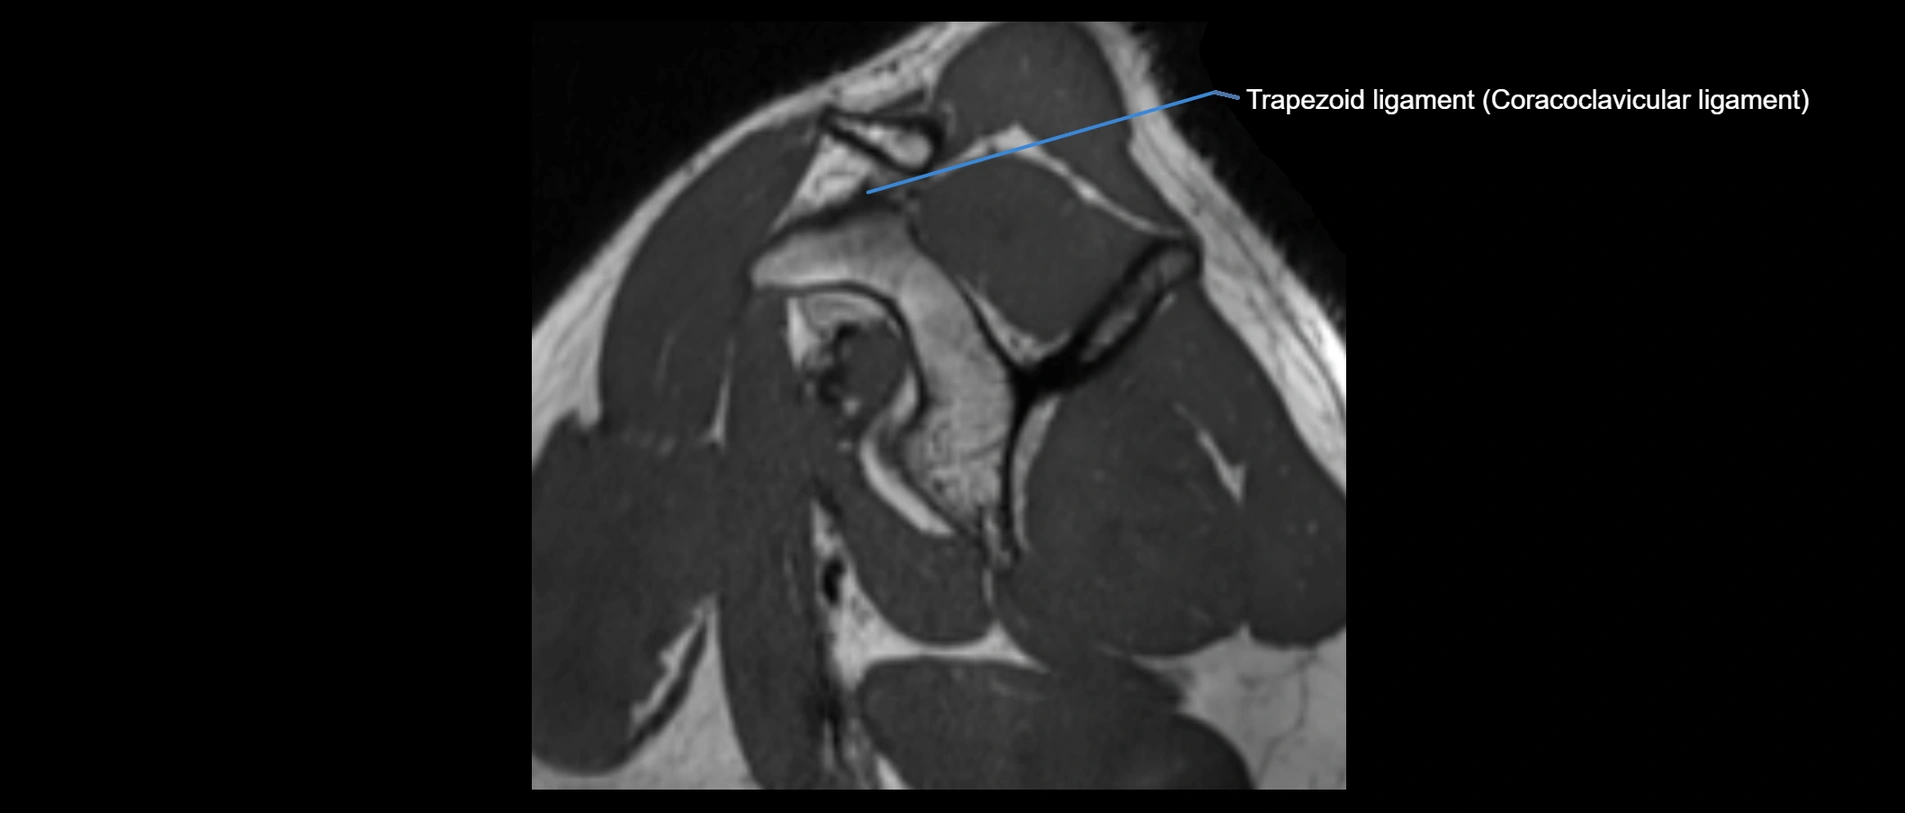

MRI images

image